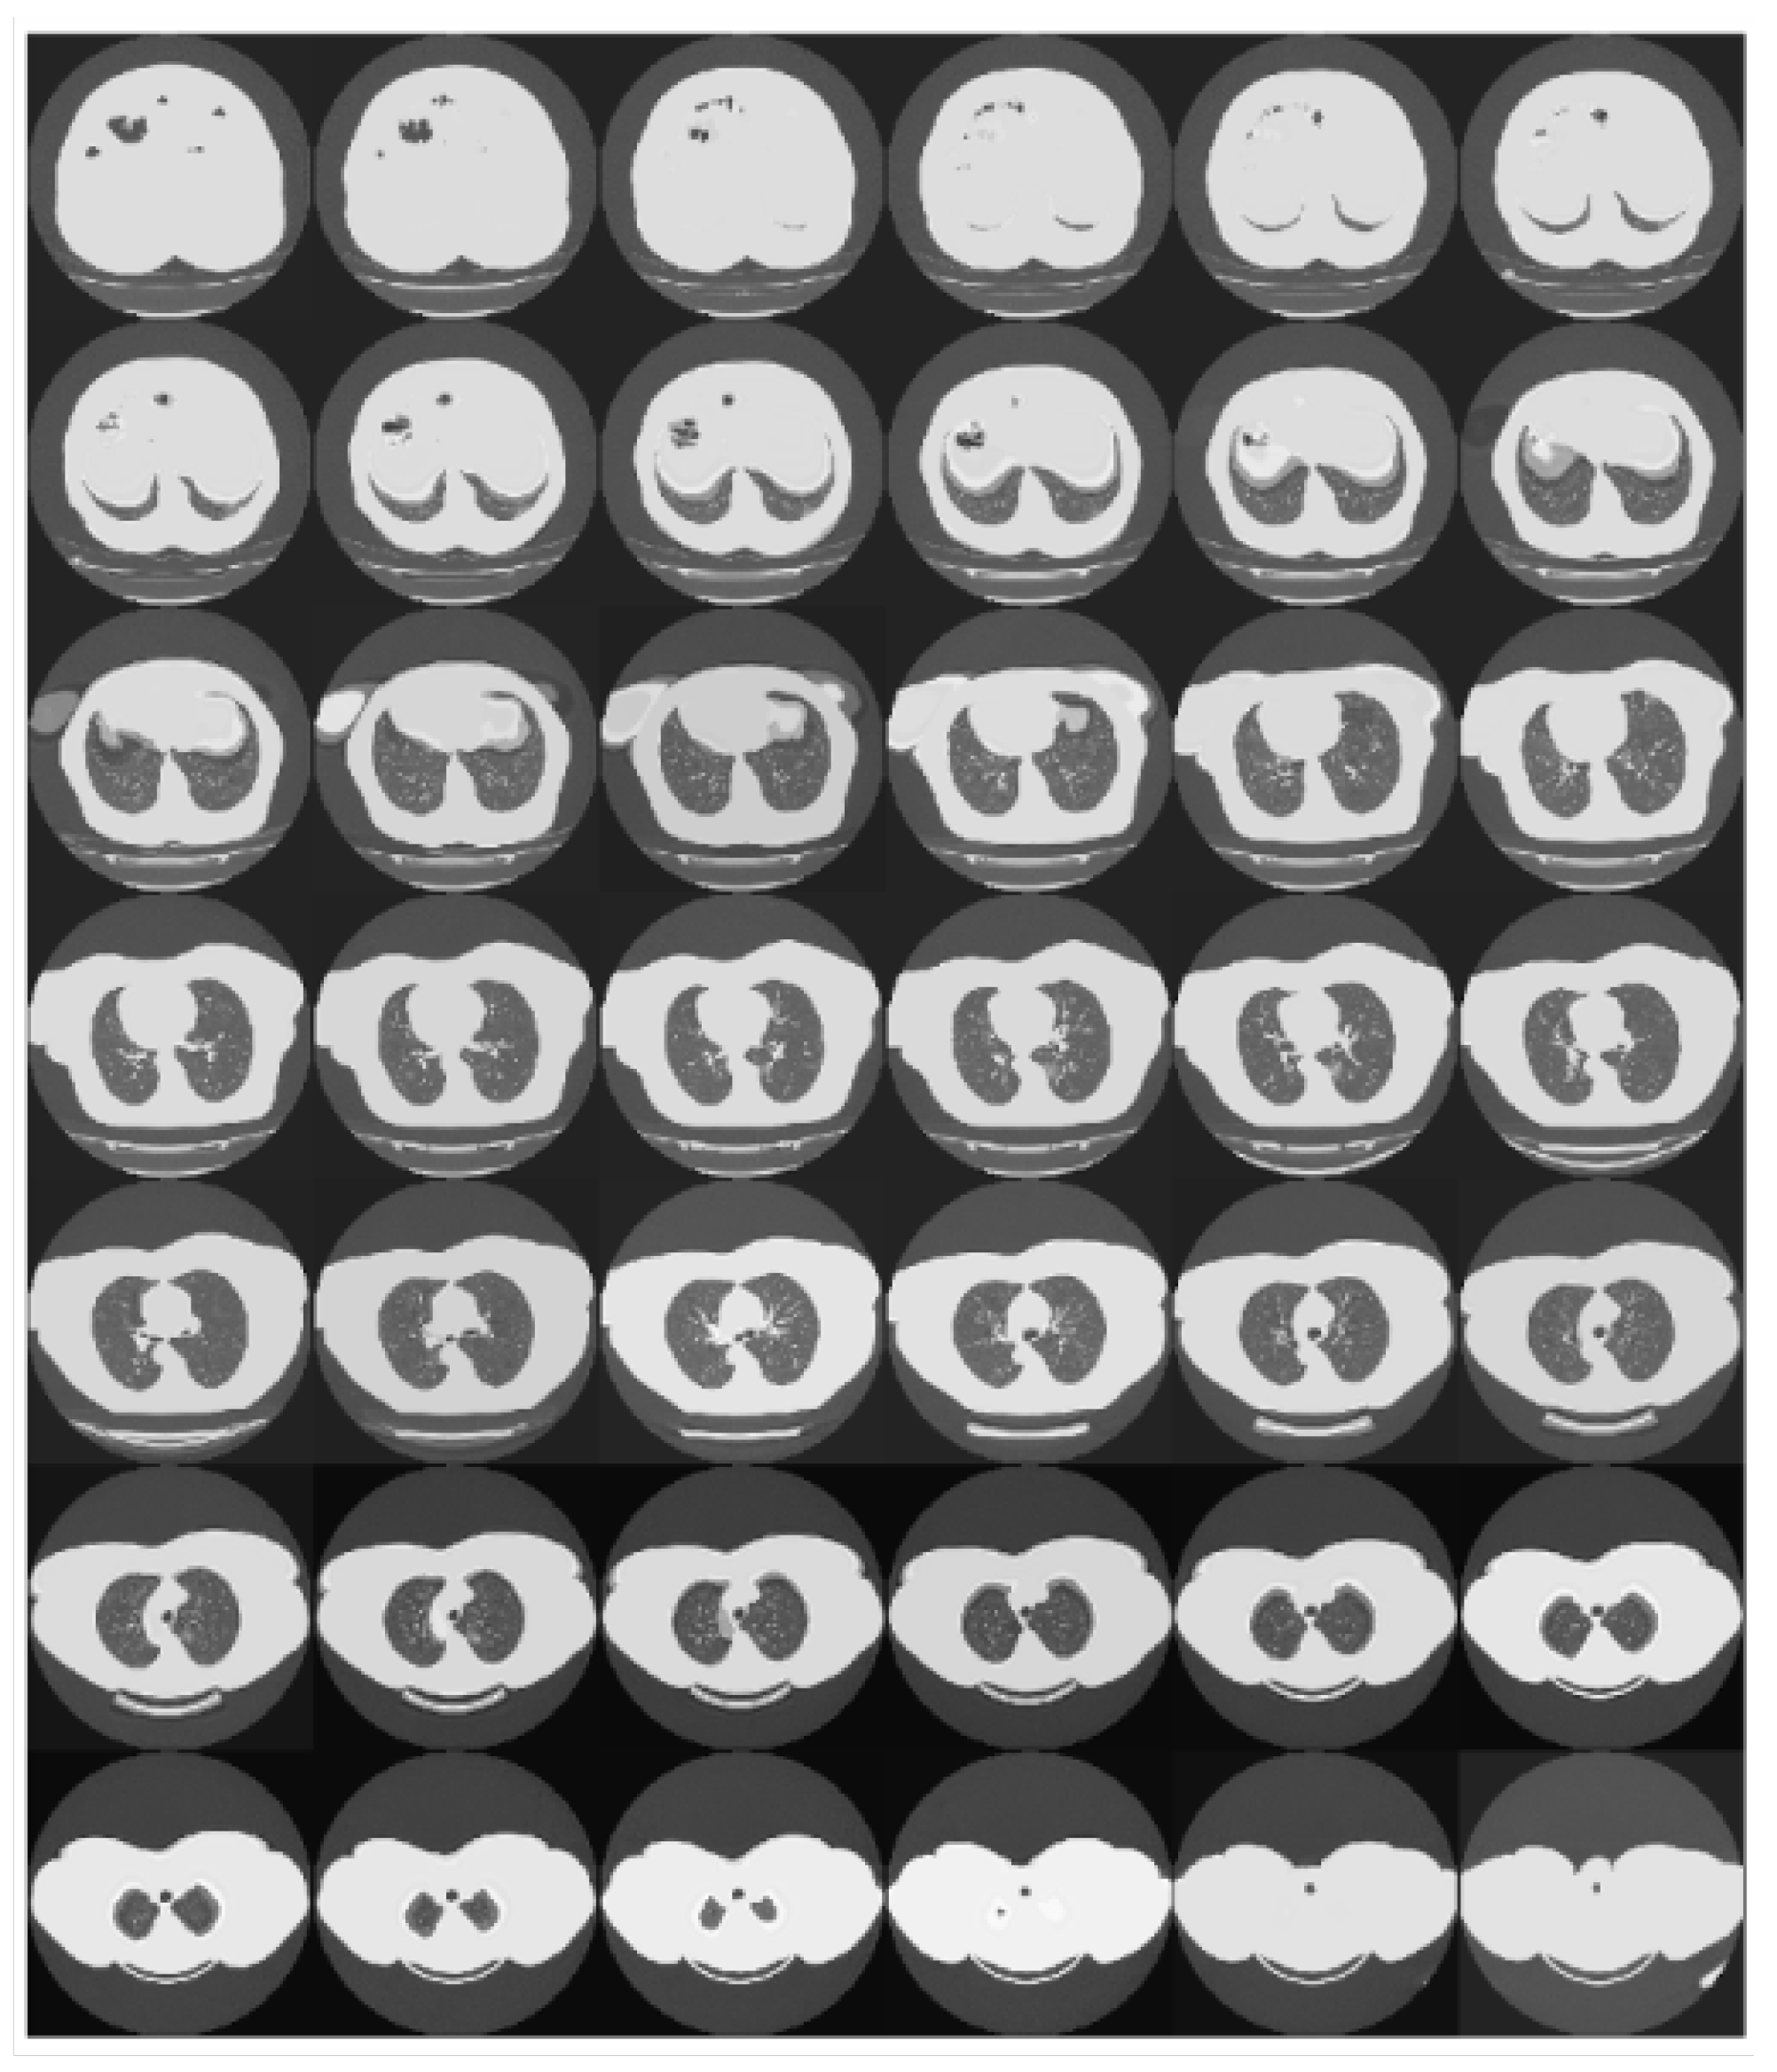

This pre-processing step has required to down-sample or over-sample the CT scans according to their original depth. The adopted strategy to perform these operations was to work at the ends of the scans, where generally, the information content is lower (see Figure 5). Basically, the oversampling was implemented by replicating the slices at both ends. Similarly, the downsampling was implemented by removing the slices starting from the ends.

Figure 5.

The figure shows the slices of a chest scan. It can be observed that the information content of the scan tends to reduce moving toward its ends.